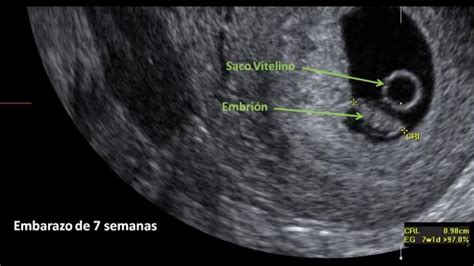

Se describe la evaluación prenatal, incluyendo la identificación del embarazo a partir de las 10-12 semanas por ultrasonido y la evaluación del tamaño uterino desde las 12 semanas. Se menciona la importancia de la evaluación semanal en consultorios externos.

Se menciona la evolución de la obstetricia, desde sus inicios hasta los avances tecnológicos actuales, como el ultrasonido para la identificación temprana del embarazo.